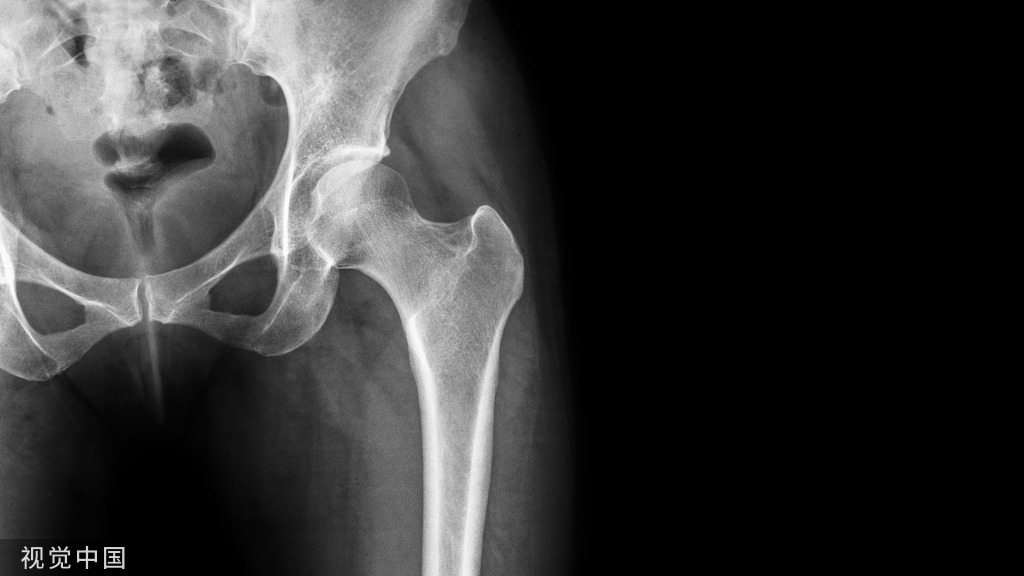

>> 关节磨损

扁平足患者由于关节错位,因此容易导致关节软骨的磨损,时间久了会导致跟腱炎、足底筋膜炎、膝盖骨腱炎等疾病症状。

>> 踝关节损伤平足畸形还有引起踝关节发生退行性改变的危险,造成不可逆的损伤。